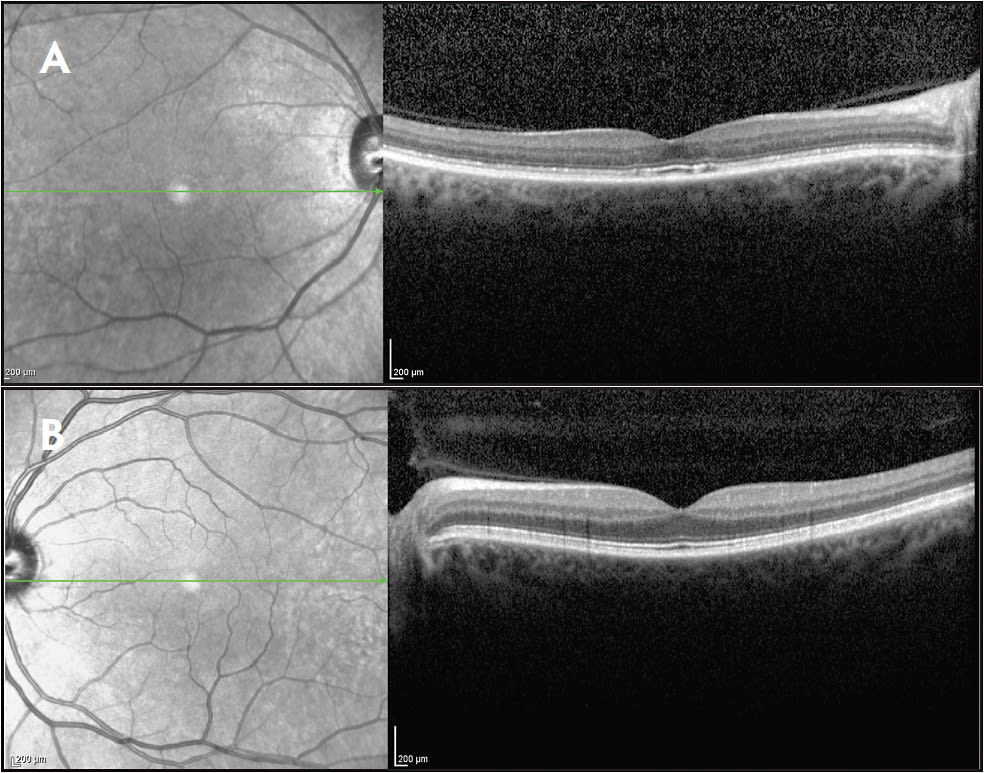

We previously reported a case of AIR that remained unilateral during an observation period of 3 years.1 The patient had an extensive history of cigarette smoking and alcohol consumption, with squamous cell carcinoma that was previously resected from the mouth and tongue. At the time of oral surgery, there was no evidence of systemic disease and the patient did not undergo any prior radiation or systemic chemotherapy. The patient presented 11 years later with a visual acuity of 20/20 in both eyes and a chief complaint of central scotoma in the right eye. Fundus examination revealed macular granularity and attenuation of the arteries and veins (Figure 1). Optical coherence tomography (OCT) displayed diffuse disruption of the photoreceptor ellipsoid zone (EZ) (inner segment-outer segment [IS-OS] junction) throughout the macula. The OCT of the left eye was normal (Figure 2).